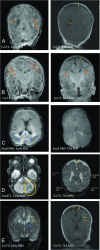

FIG 1.

WMI as appreciated in early (1T scanner) versus TEA MR imaging (3T scanner) in different cases. A, The image on the left shows an early MR imaging and the extent of WMI (orange arrows) and its evolution at TEA (image on the right) in which there is an absence of visible WM lesions. WMI sequelae can be appreciated as volume loss, with arrows indicating a dilated ventricle and enlarged subarachnoid space (yellow arrow). B, Early T1 images show severe WMI (orange arrows) with reduced conspicuity at TEA but with some volume loss. C, Early MR imaging at day 3 of life shows diffusion restriction in WM (blue arrows), which has resolved at TEA. D, Isolated unilateral cerebellar hemorrhage (encircled in yellow) with eventual disparity in cerebellar hemispheric sizes and bilateral cerebral WM volume loss at TEA. E, Early IVH (blue arrow) with dilation resulting in periventricular WMI (orange arrows) with cyst formation (green arrows) and volume loss (yellow arrows) at TEA.